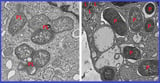

Researchers identified a 53-gene signature that differentiates inflammatory macrophages from tissue-healing macrophages in the gut, illuminating how macrophage states influence Crohn’s disease.

Within both diseased and healthy colon tissue, girdin emerges as a key protein in non-inflammatory, tissue-healing macrophages, as revealed by the gene signature analysis.

Mouse studies show that loss of girdin leads to gut microbiome imbalance, intestinal inflammation, and a higher risk of sepsis, underscoring the critical NOD2–girdin interaction in gut health.

In non-inflammatory macrophages, a region of NOD2 binds girdin to suppress excessive inflammation, clear microbes, and promote tissue repair, while most common Crohn’s mutations delete this girdin-binding region, causing imbalance.